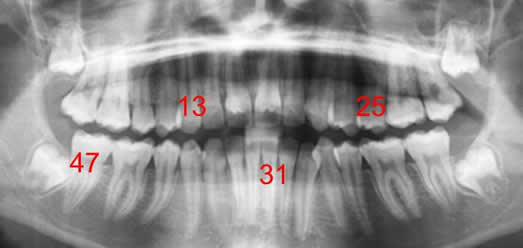

Ejemplo: (Fig 12).

Fig 12. Numeración de las piezas.

Rx panorámica.

Pieza 13: Colmillo del maxilar, en el lado derecho.

Pieza 31: Incisivo medial, del lado izquierdo de la mandíbula.

Pieza 25: 2ª premolar izquierdo, del maxilar.

Pieza 47: 2º molar mandibular derecho.